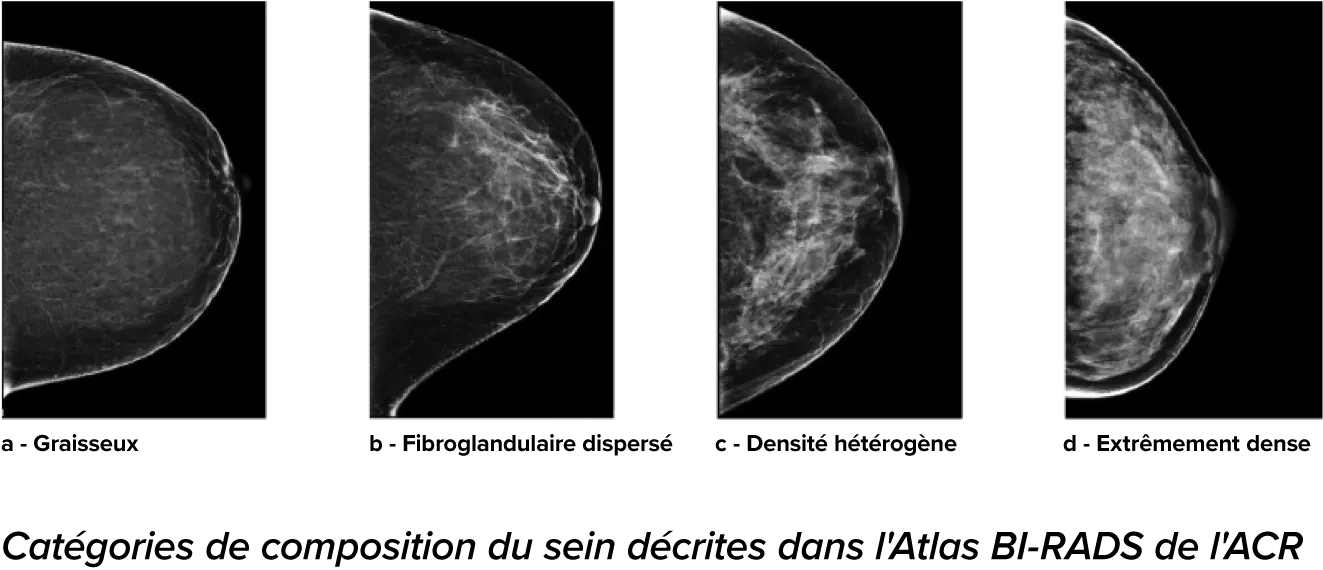

On sait qu’une densité mammaire plus élevée augmente le risque de cancer du sein chez la femme.1 Une analyse précise et objective s’avère donc primordiale. Optimisé par l’apprentissage automatique, le logiciel de la technologie Quantra analyse les images 2D™ et de tomosynthèse pour déterminer la distribution et la texture du tissu parenchymateux. Il classe les seins selon quatre catégories de composition, conformément aux recommandations de l’American College of Radiology (ACR) BI-RADS Atlas 5th Edition.2

*Les scores sont basés sur les catégories de l’ACR BI-RADS, conformément aux recommandations révisées par l’American College of Radiation (ACR) BI-RADS Atlas 5th Edition. Cela permet de tenir compte de l’anatomie et de la texture, par rapport au volume, lors de la détermination de la densité.

8. Catégories de composition du sein décrites dans l’ACR BI-RADS Atlas.